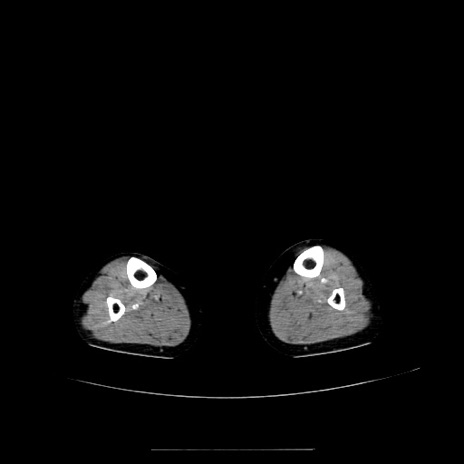

症例5(横断像)

【症例】70歳代女性

【主訴】お腹が張る

【現病歴】1週間くらい前から腹部膨満の自覚あり。昨日夜から増悪したため、本日救急外来受診。

【身体所見】意識清明、BT 36.5℃、BP 165/106mmHg、HR 80bpm、SpO2 98%、腹部:膨満、軟、自発痛・圧痛なし、触診にて不快感あり、腸蠕動音:減弱

【データ】WBC 12600、CRP 1.04